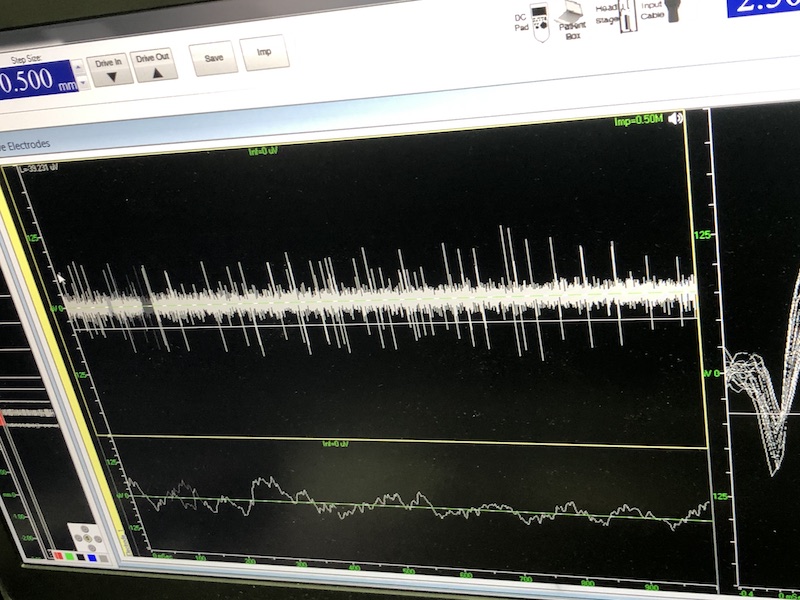

與此同時,檢測電極實時記錄電極末端每一點處的電信號,當電極逐漸接近手術規劃靶點時,借助電信號的特征,醫生可以判斷電極是否已經沿長軸植入患者顱內的目標核團,以及植入的準確長度。下圖中,檢測信號屬于典型的核團信號,證明電極已經抵達相對理想的植入位置,記錄下此刻的位置后,即可在相應位置植入刺激電極。

alt text

檢測核團信號